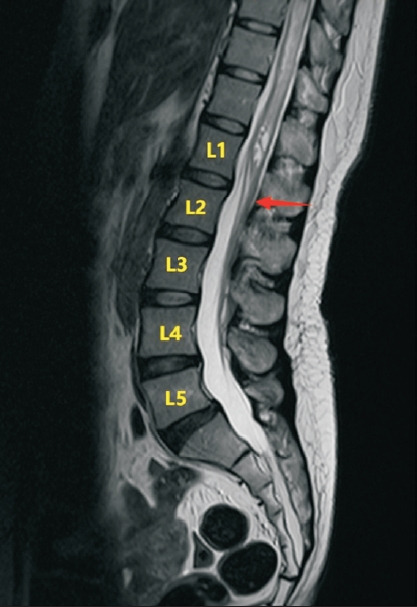

Chiari malformation type I (CMI) is a structural abnormality characterized by cerebellar tonsil herniation through the foramen magnum, often leading to disrupted cerebrospinal fluid dynamics and syringomyelia. While CMI commonly presents with occipital headaches and neck pain, atypical manifestations, such as bilateral foot drops, are exceedingly rare. We describe a 37-year-old female patient presenting with bilateral foot drop, which was later established to be caused by syringomyelia secondary to CMI. Magnetic resonance imaging revealed an 8 mm tonsillar descent and a syrinx extending to the conus medullaris. The patient refused surgical intervention and opted for conservative management; partial functional recovery was subsequently observed. This report emphasizes the importance of recognizing rare neurological presentations of CMI. To our knowledge, this is the first documented case of CMI with syringomyelia presenting as a bilateral foot drop.